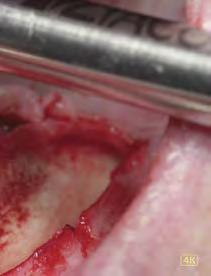

–Corticotomías y Ortodoncia. Ampliando límites del movimiento dental, por la Dra. Aranzazu Senosiain y cols. [50]